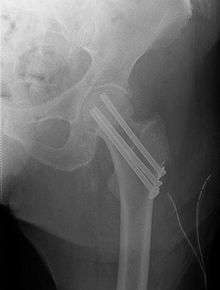

Intertrochanteric fracture

An intertrochanteric fracture, below the neck of the femur, has a good chance of healing. Treatment involves stabilizing the fracture with a lag screw and plate device to hold the two fragments in position. A large screw is inserted into the femoral head, crossing through the fracture; the plate runs down the shaft of the femur, with smaller screws securing it in place.

The fracture typically takes 3–6 months to heal. As it is only common in elderly, removal of the dynamic hip screw is usually not recommended to avoid unnecessary risk of second operation and the increased risk of re-fracture after implant removal. The most common cause for hip fractures in the elderly is osteoporosis; if this is the case, treatment of the osteoporosis can well reduce the risk of further fracture. Only young patients tend to consider having it removed; the implant may function as a stress riser, increasing the risk of a break if another accident occurs.